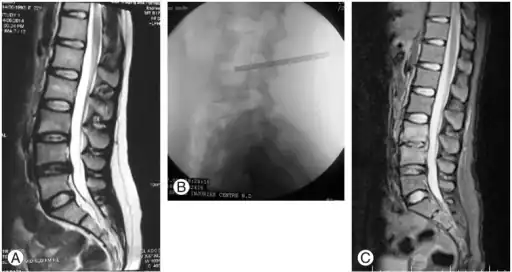

a) Atypical magnetic resonance imaging presentation via T2-weighted image b) Percutaneous intradiscal biopsy was performed from the lumber 3–4 disc c) Follow-up MRI revealed the T2-weighted image after conservative treatment showing resolution of disease